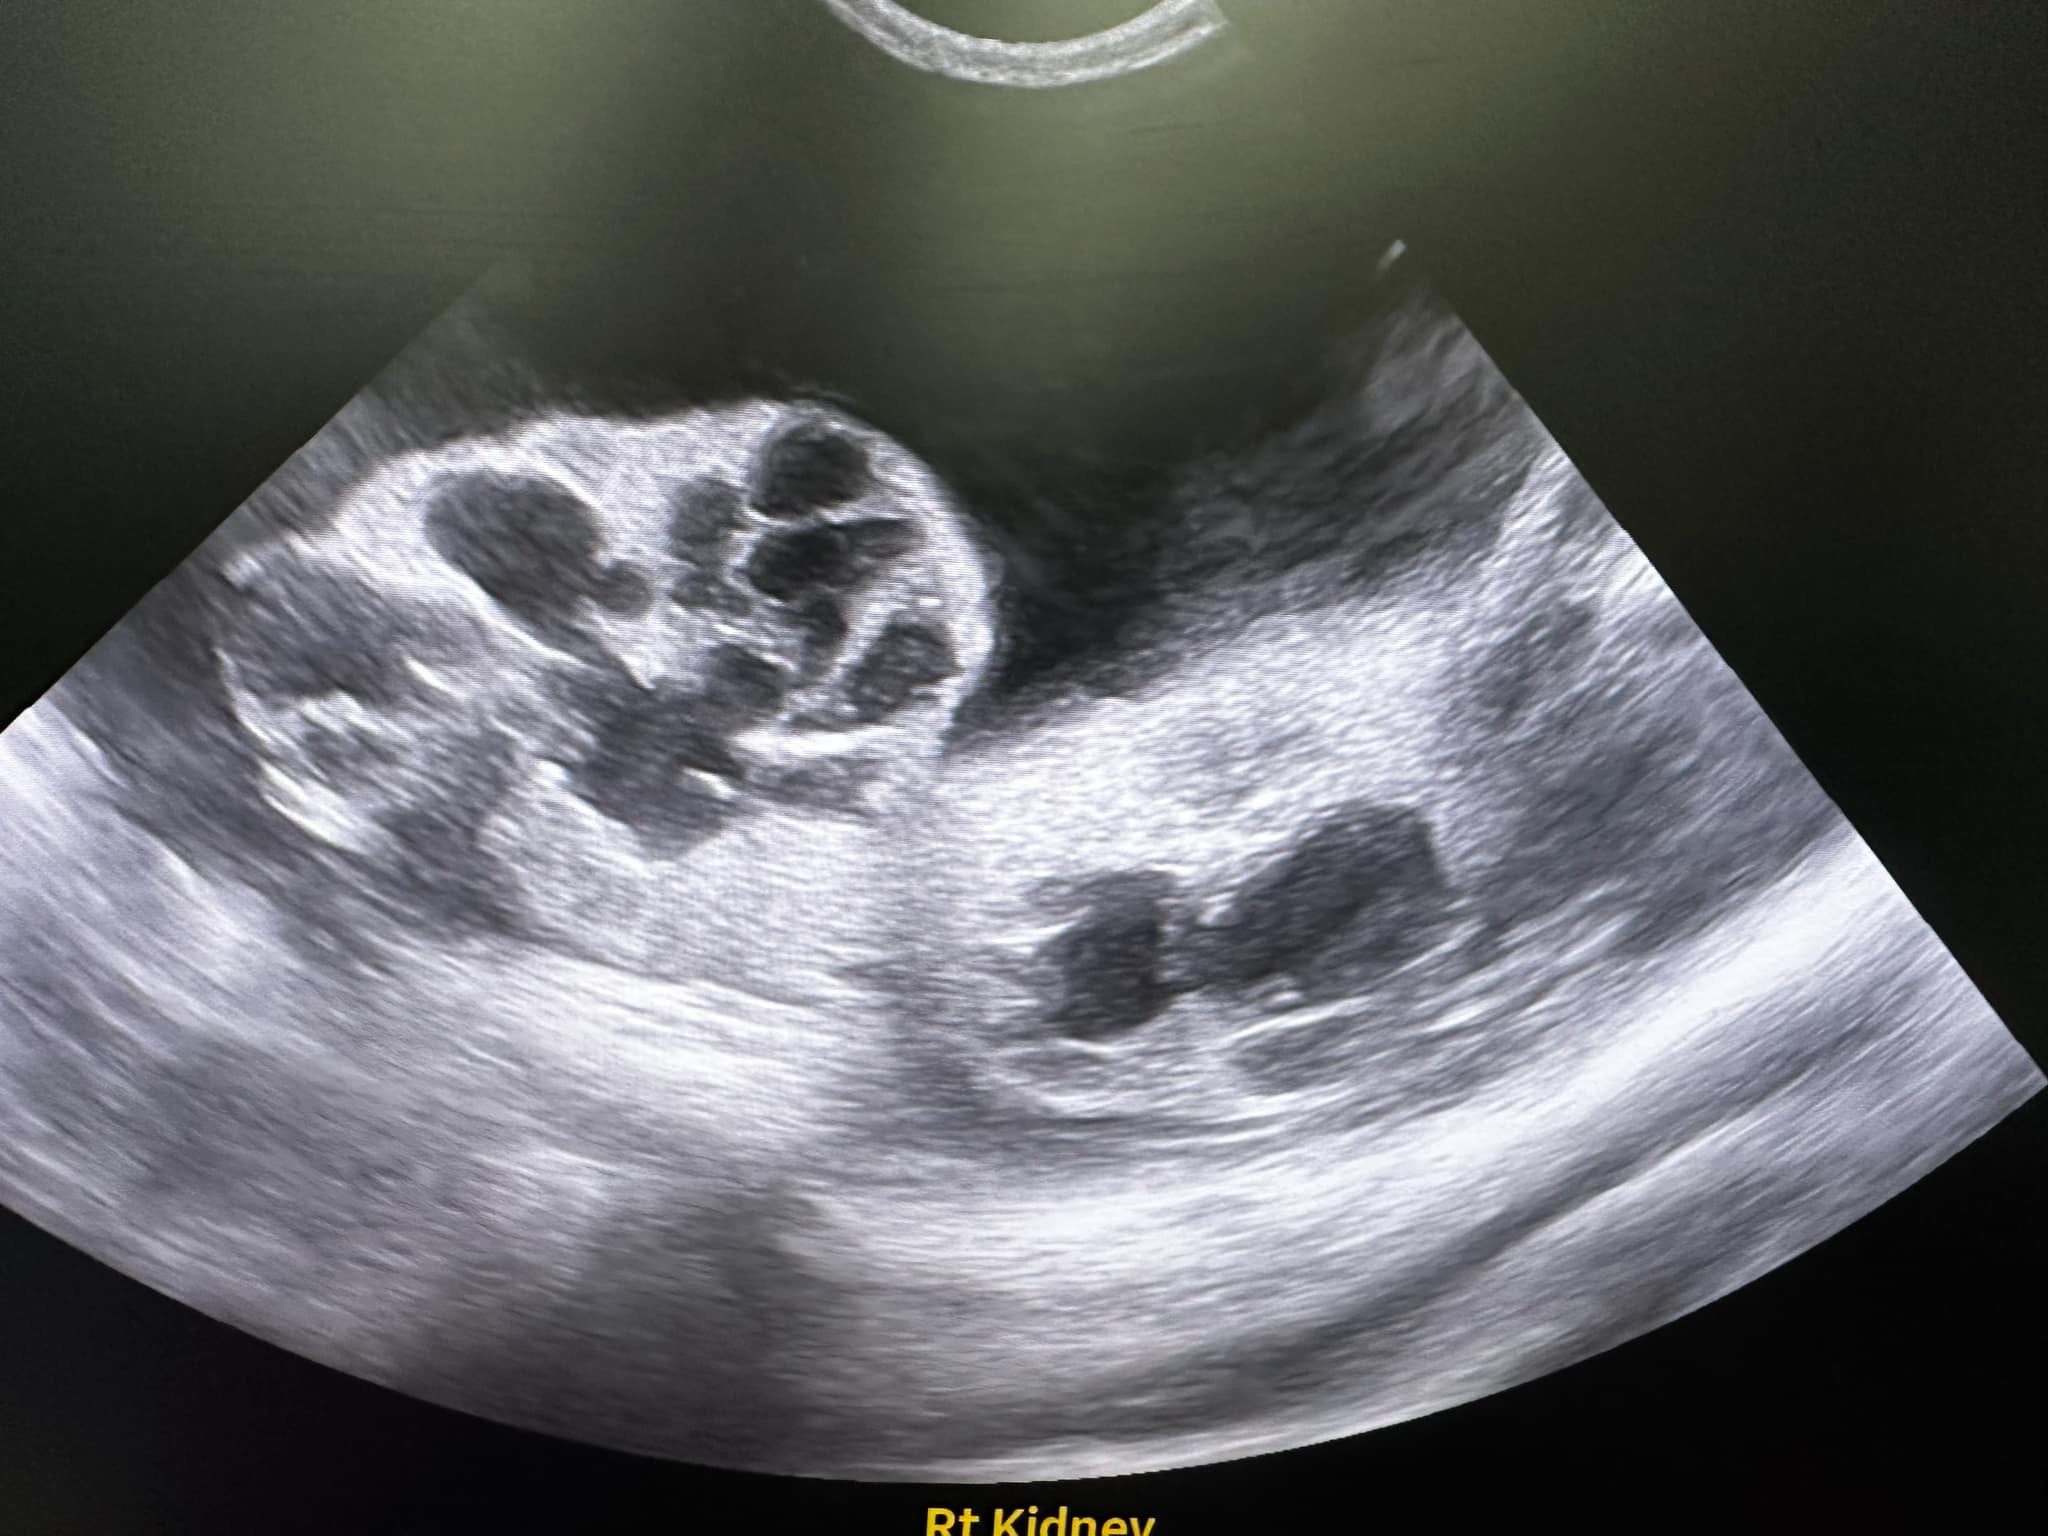

10.33am: dr d show me an u/s says don don kidney r the worst she had ever see, full of cysts for both kidneys. She remember Raichu so this family has a bad gene of cysts issue pass down. Don fluid r ard the kidneys, not the same as norm cats who had fluid ard the intestine, she said dr ym says it’s the same as last time, so she is confident of tapping, will do it away fr the kidneys. But the tapping won’t stop the cyst from leaking again. (Dr d mention more them twice that cysts r painful) noted that the tapping is more benefial to don don, only damage is my pocket) and the coming back is next time biz (maybe monthly tapping see how first).

11.38am: seen dr nally. She did hear mur mur. 3.48kg – gain 220g in 3 days, gain fluid. Taken a quick u/s scan, his cysts are all surrounded by a big ball of fluid (scary as in not sure is it the kidney itself, if yes, means the kidney super swell) or ???! N yet there are still some (little) free fluid outside the ball. For both side. Rejected the tapping. Too dangerous, might just burst the kidney/ ball.

Dr told me to go in to see her scan – both kidneys irregular in shape, like got holes like that (pic la, but he got multiple cysts on his kidneys) liver ok.